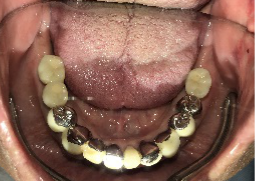

女性Mさん 40代(インプラント)

主訴

下、左右歯がないところに歯を入れたい。

治療内容

右下に2本、左下に1本インプラントを入れました。

所感

下顎左右奥の歯がないところに、インプラント治療を希望されて来院されました。X-Guideを使用し埋入しました。治療後「左右の奥歯でしっかり噛めてうれしいです。」と、とても喜んでくださいました。

インプラント3本:¥363,000×3本=¥1,089,000(税込)

Before

After